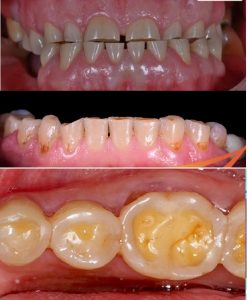

• Răng nhạy cảm, dễ ê buốt khi tiếp xúc với thực phẩm có vị chua, ngọt hoặc nhiệt độ nóng, lạnh

• Răng đổi màu do lớp men bảo vệ bên ngoài bị mài mòn. Dẫn đến làm lộ phần ngà răng bên dưới

• Mòn răng sinh lý có thứ tự mòn tương đối ổn định: Mòn ở các vị trí chịu lực trước. Mòn rìa cắn răng cửa trước, sau đó đến đỉnh múi của răng hàm (múi ngoài răng dưới và múi trong răng hàm trên) – là những vùng chịu lực nhai nhiều nhất. Đối với răng cửa sẽ mòn rìa cắn theo chiều từ trong ra ngoài ở răng trên và ngược lại đối với răng dưới.

• Hình dạng tổn thương: Ở giai đoạn mòn men, tổn thương có dạng phẳng. Khi chuyển sang giai đoạn mòn ngà, tổn thương có dạng lõm đáy chén và chuyển màu nâu do tốc độ mòn của ngà nhanh hơn men.

Tổn thương thường lan rộng và ít có giới hạn. Vị trí tổn thương nằm ở các răng gần nhau nơi bị hóa chất phá hủy mạnh nhất. Nguồn acid có thể từ: nước ngọt có gas, trái cây chua, nước chanh, giấm, trào ngược dạ dày thực quản

• Tổn trương mòn hóa học làm bề mặt men răng trở nên trong suốt, bóng, trơn và lan rộng. Với các tổn thương lộ ngà cũng tạo thành hình lõm đáy chén, nhưng có vành trong suốt ở chu vi.